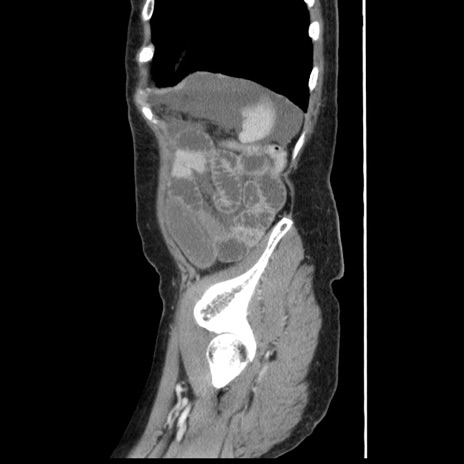

症例1(矢状断像)

【症例】80歳代女性

【主訴】腹痛

【現病歴】8時間前から腹痛あり来院。

【既往歴】糖尿病、脂質異常症、子宮体癌にて子宮全摘術

【身体所見】意識清明・会話良好だが腹痛で苦悶様、全腹部にわたって反跳痛と圧痛あり

【データ】WBC 13600、CRP 0.14、LDH 224、CK 90